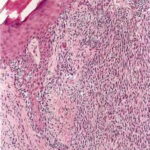

The amount of inflammatory infiltrate in tumorigenic melanomas varies. As a rule, early invasive malignant and many in situ melanomas show a bandlike inflammatory infiltrate, often intermingled with melanophages, at the base of the tumor. In tumors that extend deep into the dermis, the inflammatory infiltrate is quite variable, but it is often only slight to moderate rather than pronounced. Lymphocytes extending among tumor cells are often associated with morphologic evidence of damage to individual tumor cells (apoptosis). These tumor-infiltrating lymphocytes (TILs) have been shown to have independent favorable prognostic significance . The infiltrate is a predominantly T-cell response . TILs extracted from melanomas (mostly metastatic cases) may be cytotoxic and may be directed against immunogenic melanoma-associated antigens . |

Cytological Features. The tumor cells in the dermis show great variation in size and shape. Nevertheless, two major types of cells can be recognized; an epithelioid and a spindle-shaped cell type. Many tumors show both types of cells, but usually one type predominates. Generally, the lentiginous forms of melanoma (e.g., LMM and ALM) tend to show a predominance of spindle-shaped cells in their invasive dermal components, whereas superficial spreading and nodular melanomas tend to be composed largely of epithelioid cells . The epithelioid type of cell tends to lie in alveolar or nested formations and the spindle-shaped type of cells in irregularly branching formations. The alveolar formations of the epithelioid cells are surrounded by thin fibers of collagen containing a few fibroblasts. Tumors in which spindle cells predominate may resemble sarcomas or other spindle cell tumors but in most cases differ from them by the presence of junctional melanocytic activity. |

The uniformly atypical nuclei of the cells that constitute the tumor nodule are larger than those of melanocytes or nevus cells, with irregular nuclear membranes, hyperchromatic chromatin, and, often, prominent nucleoli that tend to be irregular in size, shape, and number. The atypia is considered to be uniform if more than 50% of the cells have these |

characteristics, but more often than not, all or most of the cells are atypical. In addition to this uniform moderate or severe cytologic atypia, there is also a diagnostically important failure of the melanocytes in the deeper layers of the dermis to decrease in size (absence of maturation) . This must not be confused, however, with the presence of an intradermal nevus beneath a melanoma, a fairly common feature. Not uncommonly, melanoma cells will recapitulate nevic cell maturation (so-called pseudomaturation), but in these instances the smaller cells at the base retain nuclear characteristics of malignant cells, and there will be cytologic continuity between these nevoid cells and the overlying more atypical lesional cells. |

Mitotic figures are usually present in the lesional cells of the dermal and epidermal compartments of tumorigenic melanomas [they are present in the epidermal lesional cells in about one third of nontumorigenic melanomas and in the dermal compartment of 85% of tumorigenic melanomas . Mitoses may also be seen in adjacent hyperplastic keratinocytes. The nuclei of these hyperplastic epidermal keratinocytes may be enlarged with prominent nucleoli, although they are not irregular or hyperchromatic. In contrast, mitotic figures are rarely seen in |